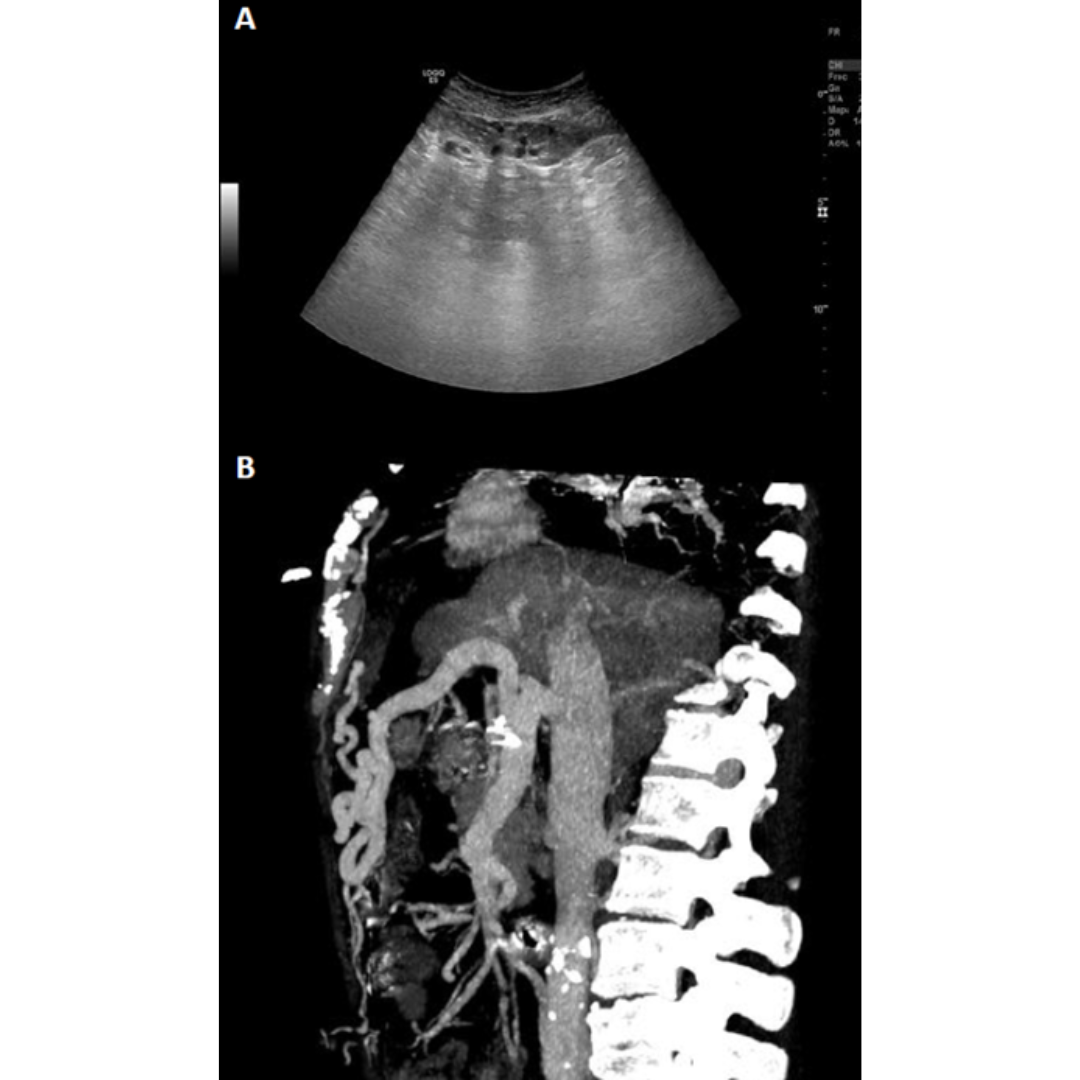

Es una enfermedad poco frecuente causada por trombosis en la vena porta que puede darse por invasión tumoral (hepatocarcinoma), por cirrosis avanzada donde el flujo hepático se ve severamente disminuido hasta trombosarse.

En estos casos se desarrolla una circulación colateral alrededor de una porta con calibre reducido y tromobosada, pudiéndose ver a nivel intra como extrahepático (figura 17 y 18 ).

Figura 17: Transformación portal cavernosa, se observan en modo B múltiples vasos serpiginosas libres de eco que reemplazan a la vena porta en hilio hepático, viéndose presencia de flujo venoso dentro de los cavernosas. (5)

Figura 18: Ramas venosas sinuosas en hilio hepático, con porta trombosada. Doppler color identifica flujo dentro de los vasos.